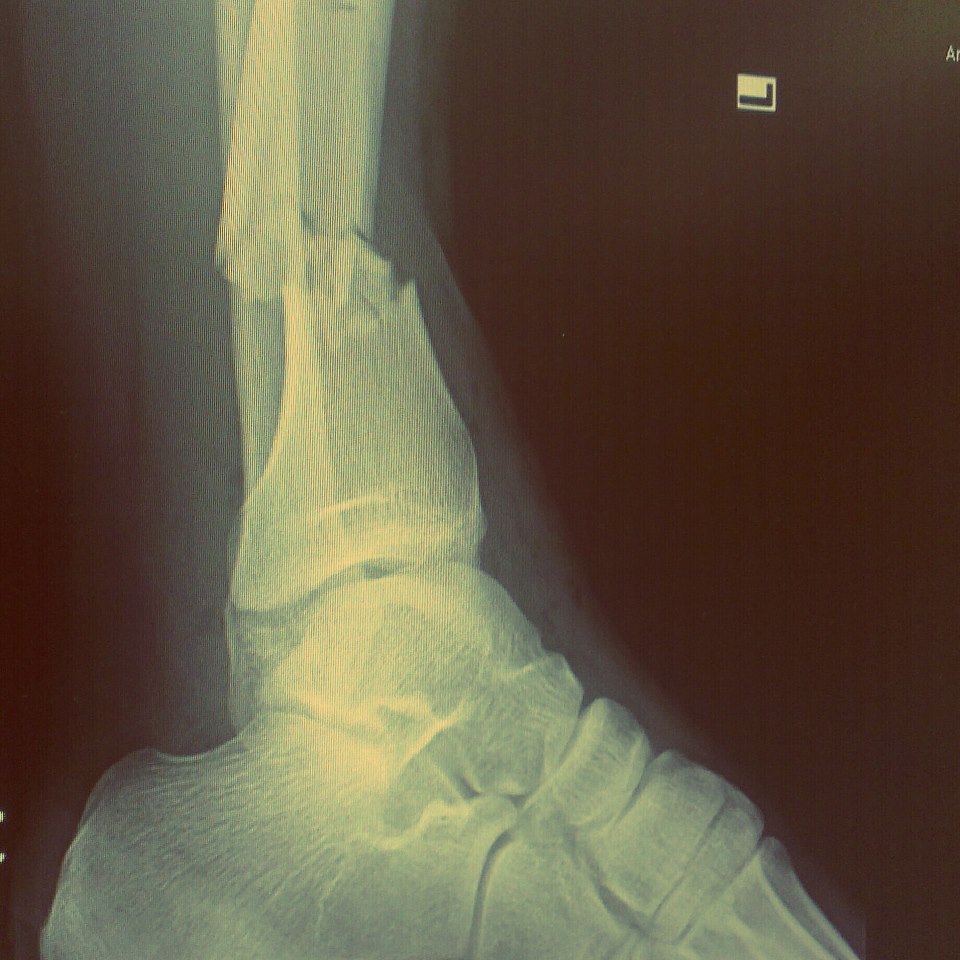

รูป X-Ray กระดูกแตก